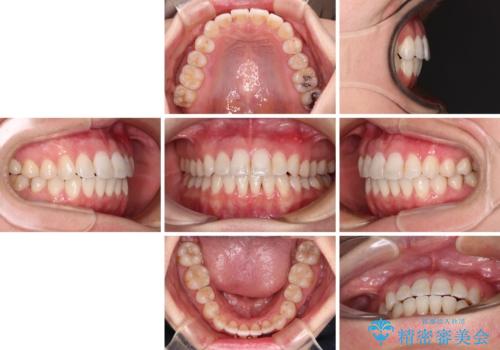

長年気にしていた前歯 インビザラインで目立たず改善

- 11ヶ月

インビザライン適用の歯列であったため、歯と歯の間を削るIPRを用いて改善することとしました。